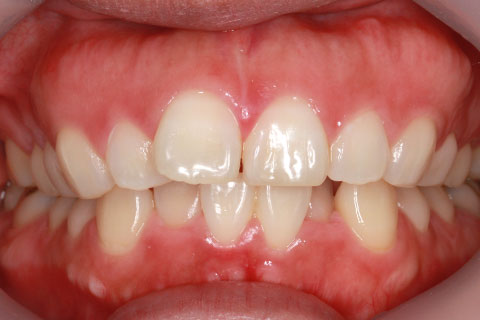

治療前

治療中

治療後

- 年齢・性別

- 25歳女性

- 治療期間

- 1年0ヶ月

- 抜歯

- なし

- 治療費

- 50万円

- 備考

- マルチブラケットを用いた矯正治療

- 治療内容

- 非抜歯にて前歯のみリンガル矯正治療。

- 施術の副作用(リスク)

- 裏側矯正の特性上、表側矯正と比較すると治療期間が長くかかる場合が多い。